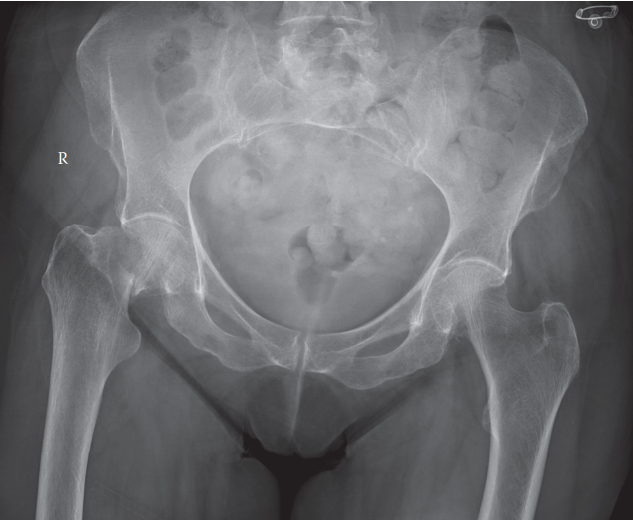

Advanced osteoarthritis bilaterally. Osteonecrosis and complete obliteration of the joint space on both sides…